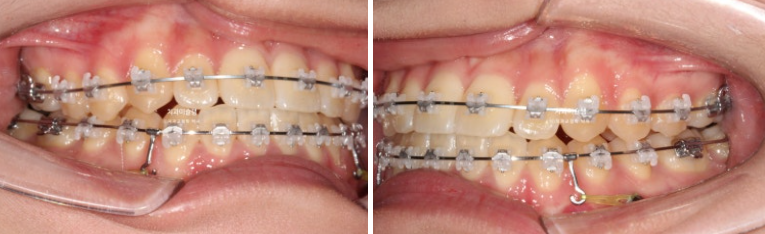

개방교합은 해소가 되었습니다.

23.09~25.07

교합은 1급 교합관계를 보입니다.

아랫니가 뒤로 들어가면서 앞니가 거꾸로 물리는 상태 즉 반대교합은 해소되었습니다.